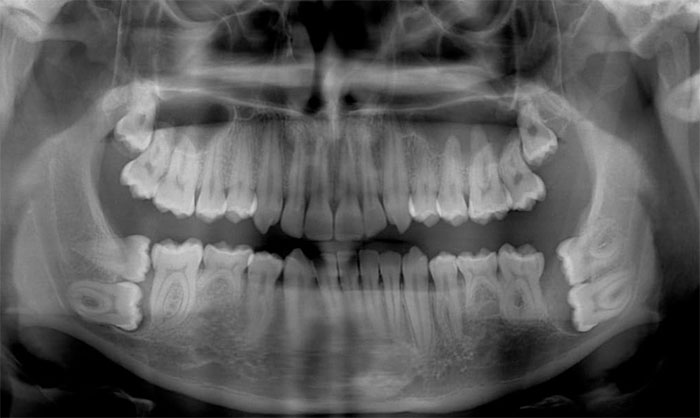

I Have A Rare Disorder Called Cleidocranial Dysotosis. Got My First Dental X-Ray Today And I Have A Lot Of Extra Teeth

X-Rays Of Children's' Mouths Between The Ages Of 6-12 Years Still Hold Wonder For Me, Even After Being A Dentist For 10+ Years